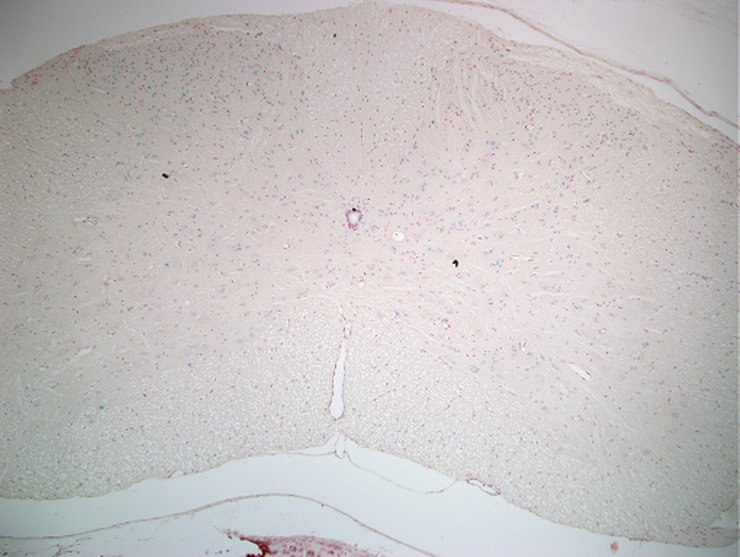

TS28: spinal cord Present TCP_1465866

TS28: spinal cord Present UC Davis_1882378

TS28: spinal cord Present TCP_1465875

TS28: spinal cord Present UC Davis_1882435

TS28: spinal cord Present UC Davis_1882436